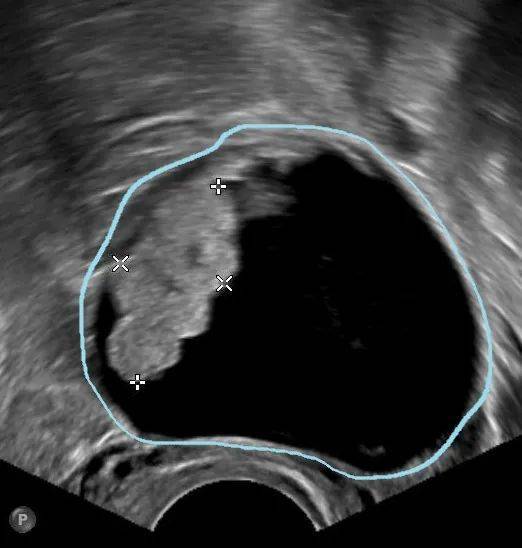

5、卵巢子宫内膜异位囊肿

卵巢子宫内膜异位囊肿的发生可能与经血逆流、淋巴及静脉扩散等因素相关。它主要会引发痛经、月经失调等 症状,血清CA125水平常轻度升高。随着病情进展,还可能出现不孕、囊肿破裂等并发症,且有恶变的可能。虽然 可以通过药物减缓其生长速度,但是最终仍可能需要进行手术治疗。